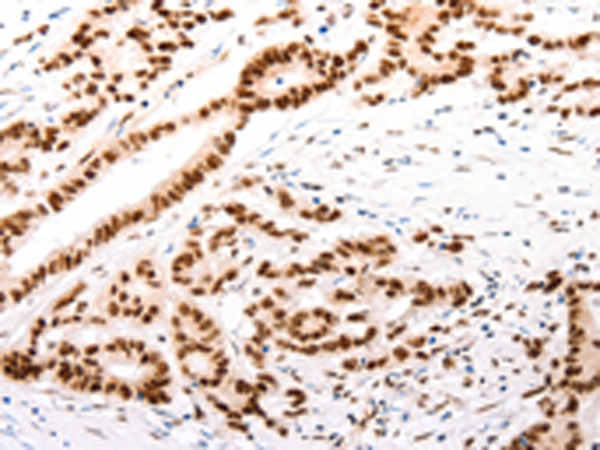

分类: 科研抗体货号: P04507别名: TAP; Sca1; Sca-1; Ly-6A.2; Ly-6A/E; Ly-6E.1应用: IHC反应种属: Human, Mouse